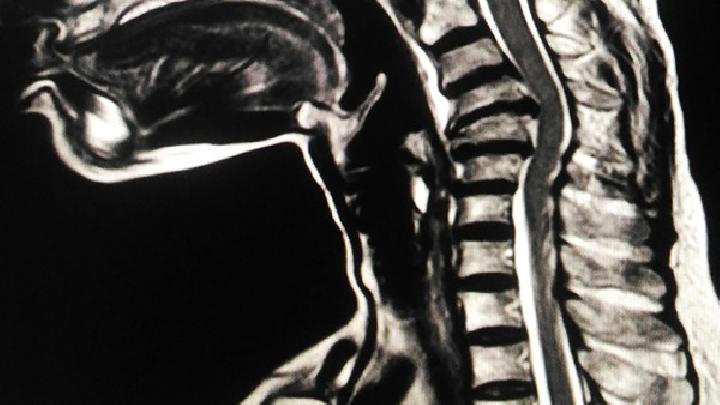

腰间盘突出

>

经常开车预防腰椎间盘突出的常见方法

腰椎间盘突出